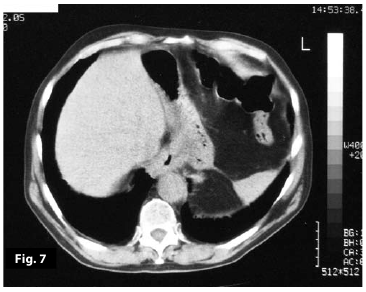

Figure7